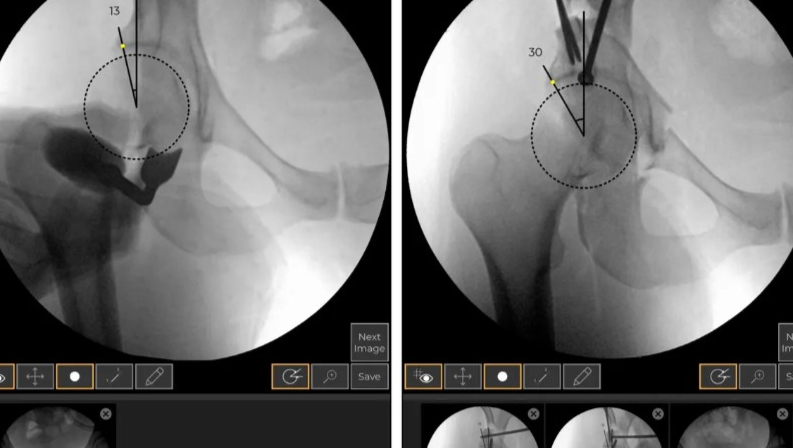

Zimmer通过收购扩大其在髋关节手术领域的市场份额